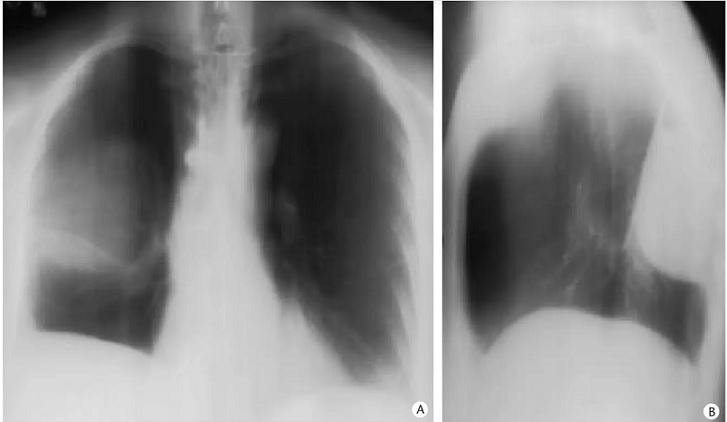

Aspect

radiologique d'une epanchement enkyste , loclise du

poumon droit en coupe de face et de propile droit .

Image radiologique en forme de " goutte d'eau " est

tres nette sur coupe de profile . Image radiologique

tomographie ( planigraphie ) pulmonaire , coupe de

face et de profile à travers la lesion |